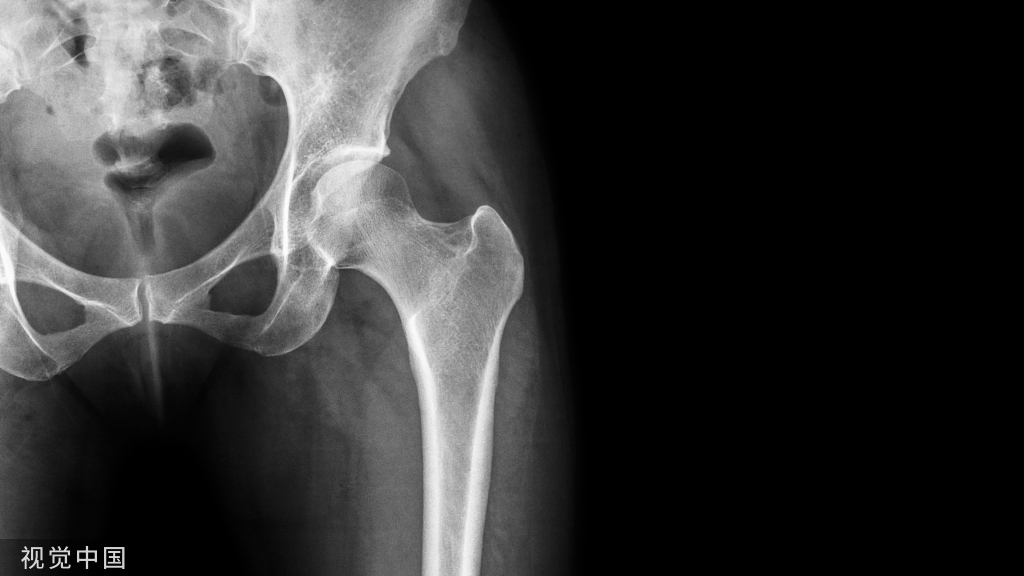

骨质疏松症是一种使骨骼变得脆弱的疾病。这大大增加了骨折的风险,即使是轻微的跌倒或撞击。据我国2018年的流行病学调查显示,50岁以上人群女性患病率为32.1%,男性为6.0%;而65岁以上人群骨质疏松女性患病率为51.6%,男性为10.7%。

骨质疏松症( osteoporosis,OP) 是最常见的骨骼疾病,是一种以骨量低,骨组织微结构损坏,导致骨脆性增加,易发生骨折为特征的全身性骨病。

一旦骨质严重流失,骨骼的内部结构将变得脆弱,距离骨质疏松就越来越近,骨头的质量和力量都被削弱,很容易导致突然和意外的骨折,也就是我们通常所说的“骨脆脆”。

骨质疏松性骨折,多见于老年女性,特别会发生在腰椎及胸椎,即出现锥体压缩性骨折,这是老年性骨质疏松症最常见和最严重的并发症。